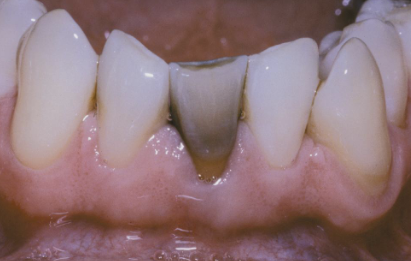

what is the diagnosis?

regional odontodysplasia